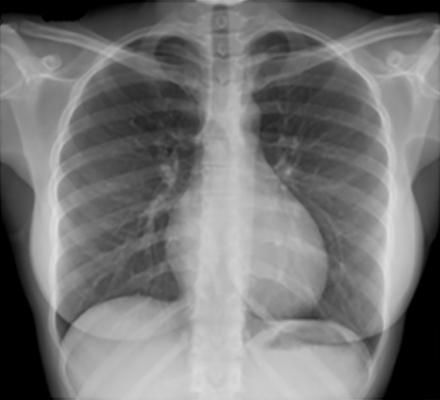

Poumon - Radio normale

1. Image

2. Poumon - Radio normale